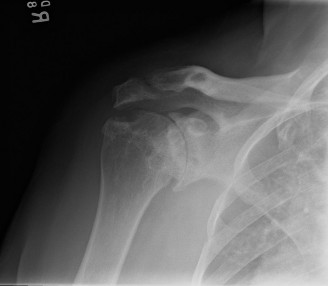

Identify the muscles that compose the force couples in the transverse and coronal planes? CASE 3 A 35-year-old male has had left shoulder pain for 4 months, ever since a low-speed motor vehicle accident (MVA). Physical examination demonstrates preserved range of motion but pain and some weakness with Jobe’s testing. His imaging is shown in Figure 2–8.

Rotator cuff tears are a common reason for shoulder pain and a common reason to obtain shoulder imaging. As a result, numerous different imaging modalities exist offering different pros and cons. Plain films are still the initial imaging modality of choice. These are most useful in ruling out other possible diagnosis but can help with the diagnosis of a rotator cuff tear as well. Changes to the tendon itself

may appear as calcific tendinosis, which would most commonly be seen at the bone–tendon interface. A decrease in the acromiohumeral distance (less than 2 mm) may also be indicative of a cuff tear. In late cases of rotator cuff tears, superior subluxation of the humerus may be evident. Certain variations in acromial anatomy, including spurs or a hook-shaped (type 3) acromions, may be associated with rotator cuff tears as well. With progression of rotator cuff tears, degenerative changes including spurs, cysts, and sclerosis may be evident at the greater tuberosity. In late, massive tears one may see degenerative changes consistent with rotator cuff arthropathy.